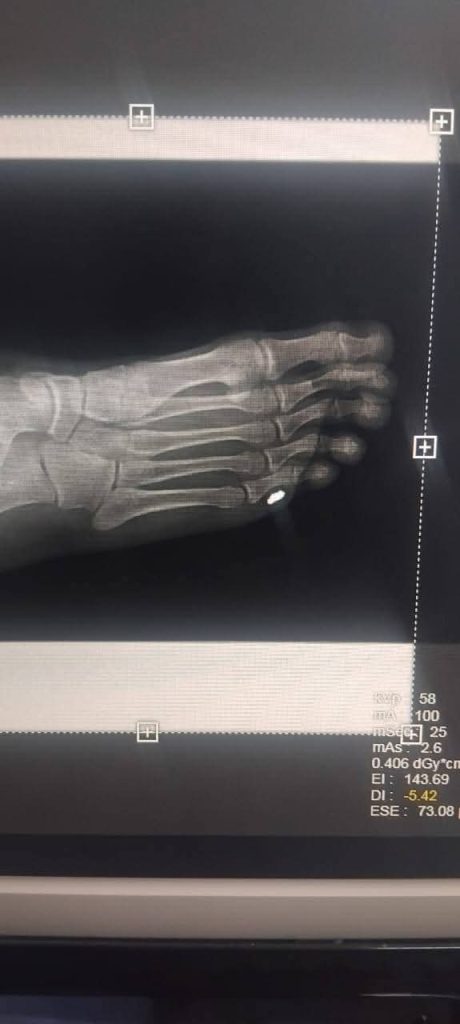

أجرى قسم العمليات والجراحة بمستشفى ققم العام، عملية جراحية صغرى ناجحة لحالة قادمة من منطقة تامزاوة كانت تعاني من إصابة بطلق من مسدس هوائي (فلوبر) في الرجل.

وأوضح المكتب الإعلامي بالمستشفى، أنه على الفور تم استقبال الحالة وتجهيزها بشكل عاجل، حيث تم تحويلها إلى قسم الأشعة لإجراء الفحوصات والتصوير اللازم، وبعد تقييم الحالة من قبل الطبيب المختص تقرر التدخل الجراحي

واشار إلى ان تم إجراء عملية جراحية صغرى تحت التخدير الموضعي، وتم خلالها استخراج الطلقة من الرجل.